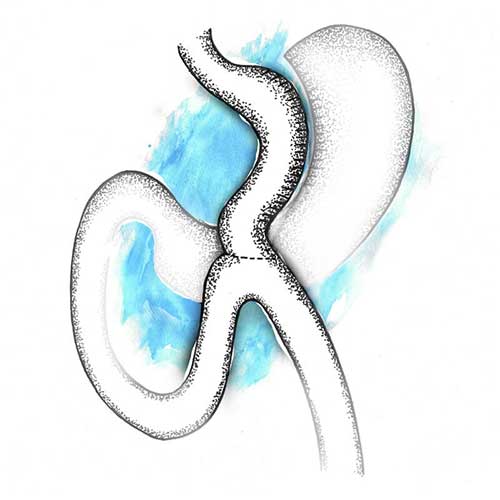

Laparoscopic mini gastric bypass is a variant of the gastric bypass surgery. It sees a loop of the small intestine being joined to the stomach pouch at a distance of 150 to 200 cm.

It is the procedure of choice for patients who do not suffer from gastroesophageal reflux disease and are aged above 50. It may also be recommended for patients on multiple anti-depressants or anti-psychotic medication.

Like other procedures, nearly 60 to 80 per cent of your excess body weight will reduce over a period of one-and-a-half years with rapid weight loss during the first three to four months after surgery. Though the chances of regaining the lost weight are negligible, it is possible if you do not follow a healthy lifestyle according to our recommendation.

Post-surgery, vitamin and mineral supplements need to be taken regularly and for life. Overconsumption of high-calorie liquids or foods may cause diarrhea. There is also a possibility of marginal ulcers and bile reflux, causing abdominal discomfort.